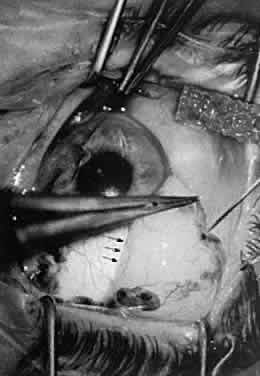

DISSECTING A FORNIX-BASED CONJUNCTIVAL FLAP

When a fornix-based conjunctival flap is dissected, several basic surgical principles are used. Ideally, there is a preexisting surgical plane through which the surgeon can use blunt dissection to separate the tissue. For the beginning surgeon, dissection of the surgical plane may be aided by injecting a local anesthetic or balanced salt solution into the subconjunctival space such that the force of injection of the fluid dissects the potential surgical plane (Fig. 38). The anatomy of the insertion of both the conjunctiva and Tenon's capsule must be familiar to the surgeon because the conjunctiva inserts more anteriorly than Tenon's capsule. These two layers may be dissected individually or together off the limbus. Some surgeons prefer to dissect these layers individually because this method allows for a cleaner dissection, with use primarily a 0.12-mm tissue forceps and blunt Westcott scissors. First, make the initial incision radial to the limbus and then use blunt dissection to separate the potential space between the conjunctival insertion and the insertion of Tenon's capsule. The conjunctiva is removed from the cornea with sharp dissection. The force applied to the scissors is toward the center of the cornea to ensure that the conjunctiva is dissected off at the corneal insertion. Tenon's capsule is picked up with the 0.12-mm forceps and incised. With blunt dissection, using Westcott scissors, Tenon's capsule is bluntly dissected from the globe by opening the scissors. The insertion of Tenon's capsule is incised by sharp dissection. Again, the force applied to the scissors is toward the center of the cornea. The beginning surgeon may tend to leave strands of Tenon's capsule on the limbus. Doing so may interfere with tying of sutures and burying of surgical knots because the small Tenon's fibers may become incorporated into the surgical knot, making it difficult to rotate the suture.

Fig. 38. A needle is inserted into the subconjunctival space. The potential space is enlarged by the force of injection of the fluid, which will identify the potential surgical plane. The junction of the elevated conjunctiva is shown (arrows).